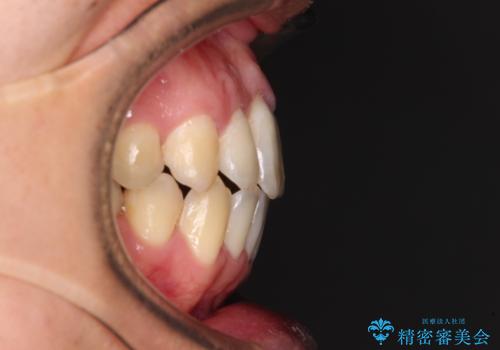

上顎歯列全体を後方に移動させたため、口元の突出感も改善され、装置を外してからは口が閉じやすくなりました。

また、上下犬歯が接触するようになったため、奥歯にストレスのかからない歯ぎしりができるようになり、顎の疲れも改善されました。